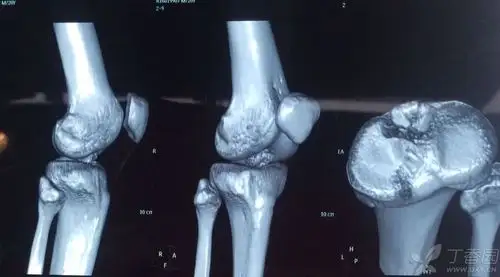

胫骨髁间棘骨折